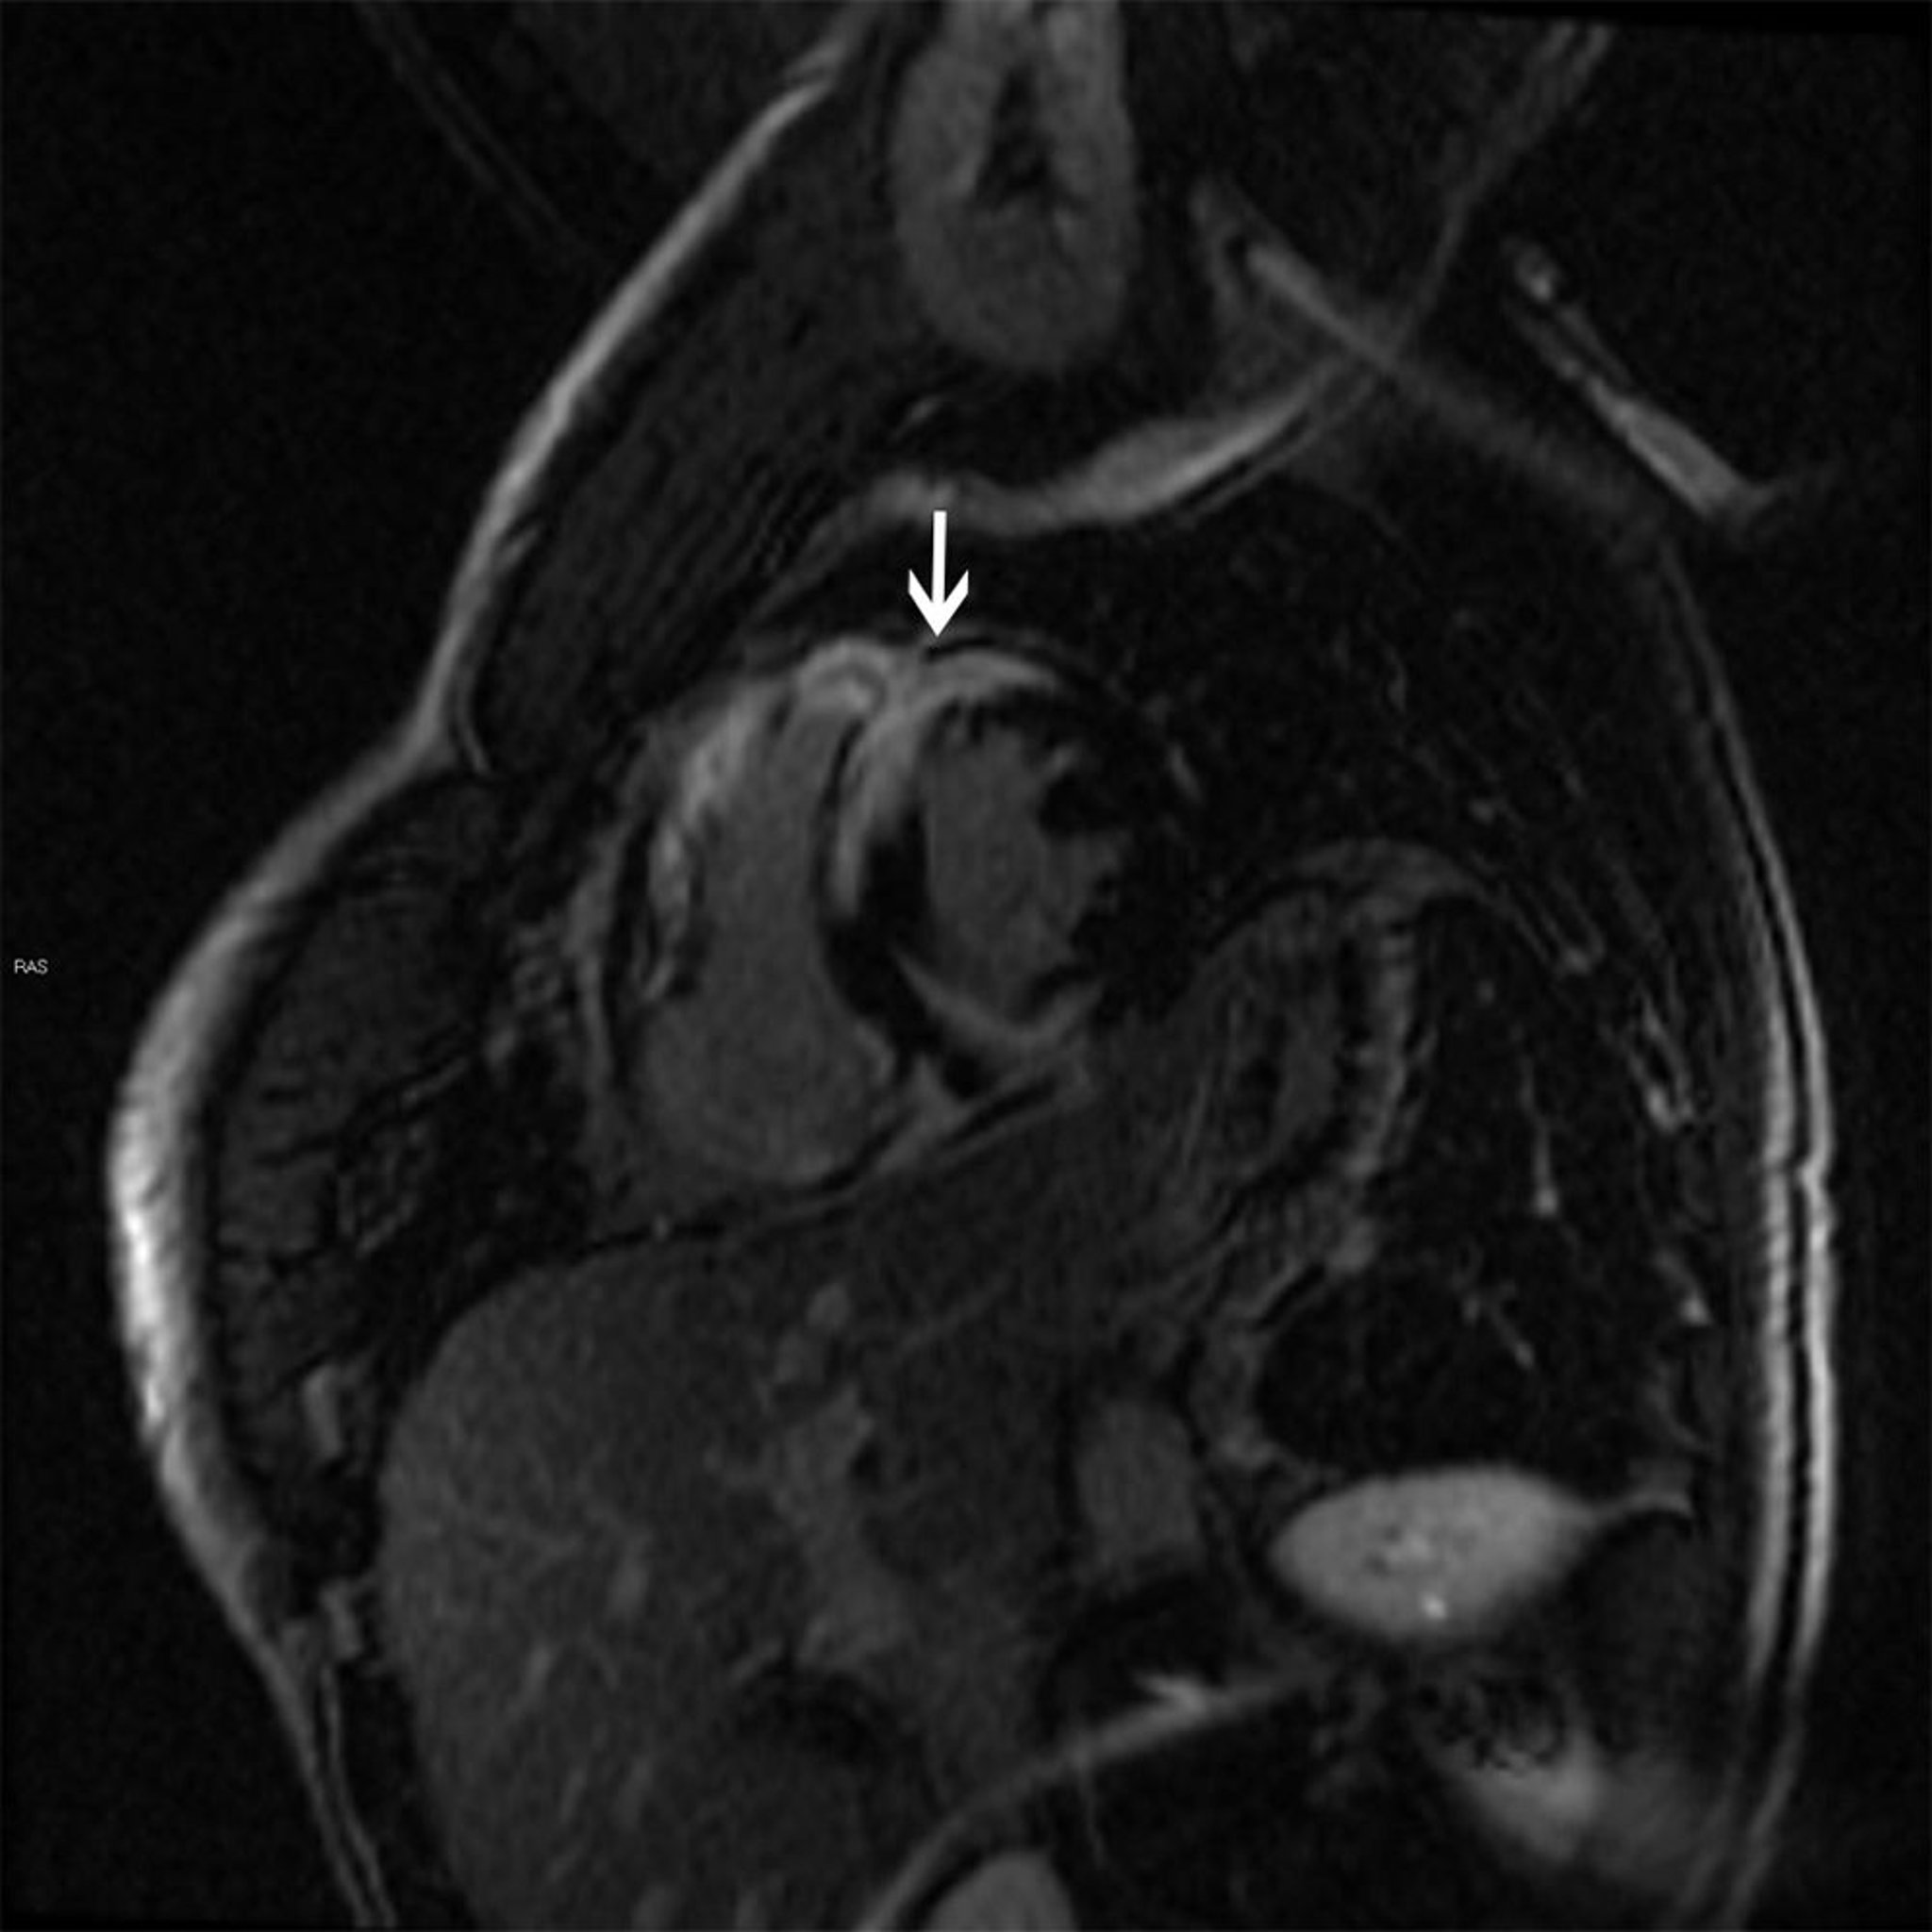

Achados na RM da sarcoidose cardíaca

Essa RM cardíaca mostra um padrão tardio irregular de realce transmural com gadolínio (seta) característico da sarcoidose, que pode causar cardiopatia dilatada ou hipertrófica.